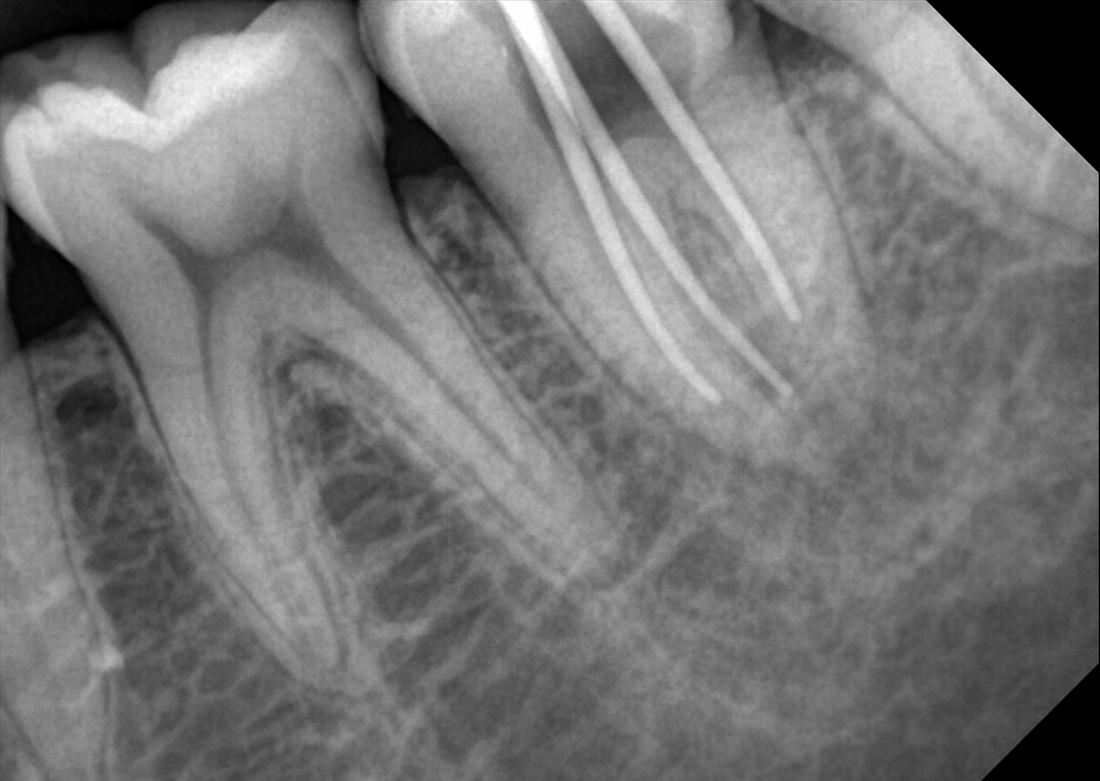

KLIMIKAI FELVÉTELEK

Hosszú tapasztalat során felhalmozott szakértelmünkkel kiváló diagnosztikai képeket biztosítunk.

Ez a Genoray büszkesége, amelyet világszerte szeretnek.